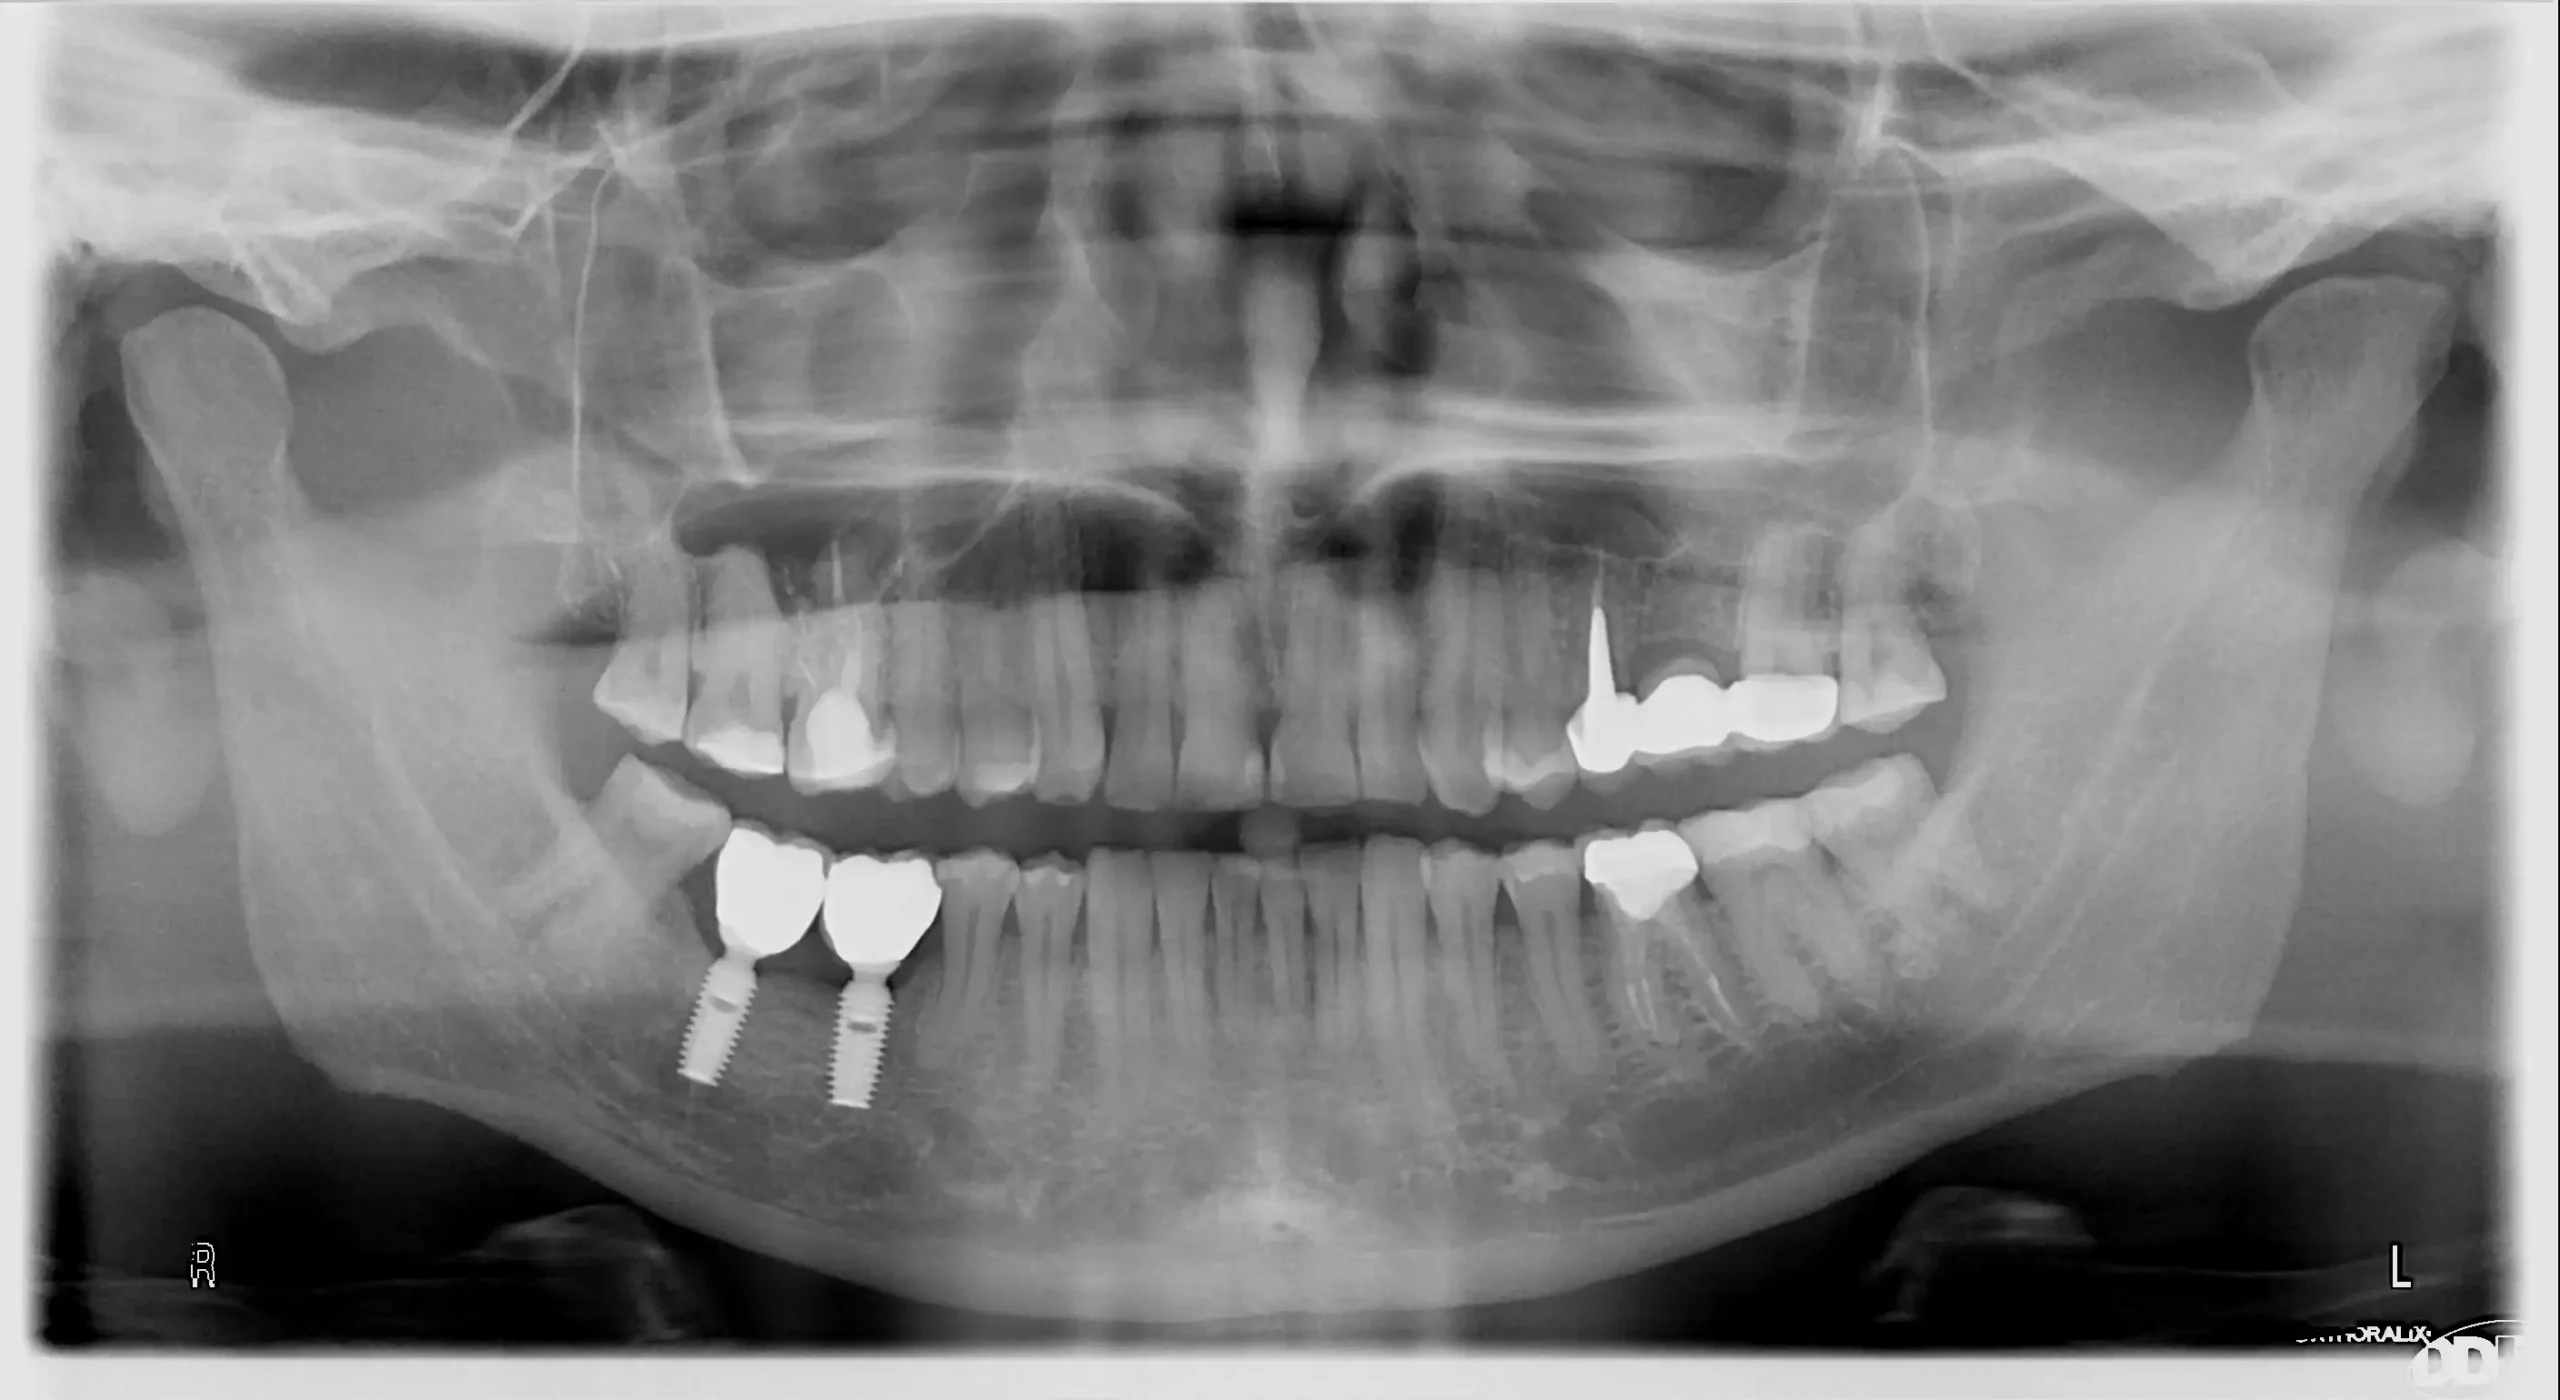

Implanty zębowe (implanty dentystyczne) to innymi słowy zamienniki korzenia zębowego, które umiejscawiane są w kości żuchwy bądź szczęki. Ich osadzenie pozwala stworzyć koronę, most lub protezę, która pozwoli uzupełnić braki w uzębieniu. Implanty zębowe to opcja, dzięki której nie maskujemy niedoskonałości, a uzupełniamy uśmiech w prawidłowo funkcjonujący oraz prezentujący się naturalnie nowy ząb. Wykonanie z biozgodnego tytanu sprawia, że organizm doskonale go przyjmuje, a prawidłowo chirurgicznie wszczepiony implant zostaje obudowany przez kość (tzw. osteointegracja), dzięki czemu ząb jest stabilny i mocno osadzony.

Sam implant na tym etapie nie uzupełnia braku w uzębieniu. Pełna funkcjonalność zapewniona jest dopiero po zamocowaniu w implancie korony, mostu lub protezy. W części protetycznej uzupełniania uśmiechu – wykonywanej po pełnym procesie osteointegracji – możliwe jest założenie nowego zęba lub zębów.